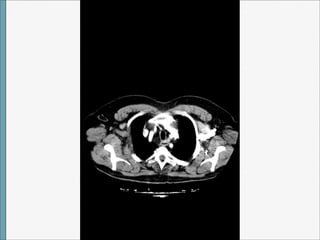

TAC

Arco Aórtico Derecho

1)CON ARTERIA SUBCLAVIA IZQUIERDA ABERRANTE

• Prevalencia:1/100. No predominio por sexo o

raza.

• Embriología: ruptura entre la arteria carótida

común izquierda y la arteria subclavia

izquierda que se origina sobre un divertículo

de Kommerell.

• Clínica: no sintomatología, hallazgo

incidental. Si presenta síntomas

relacionados con :

- Compresión esófago y tráquea por el

diverticulo o la arteria subclavia izquierda.

• -Persistencia de un ligamento arterioso

entre arteria subclavia aberrante y arteria

pulmonar.

• No relación con cardiopatía congénita